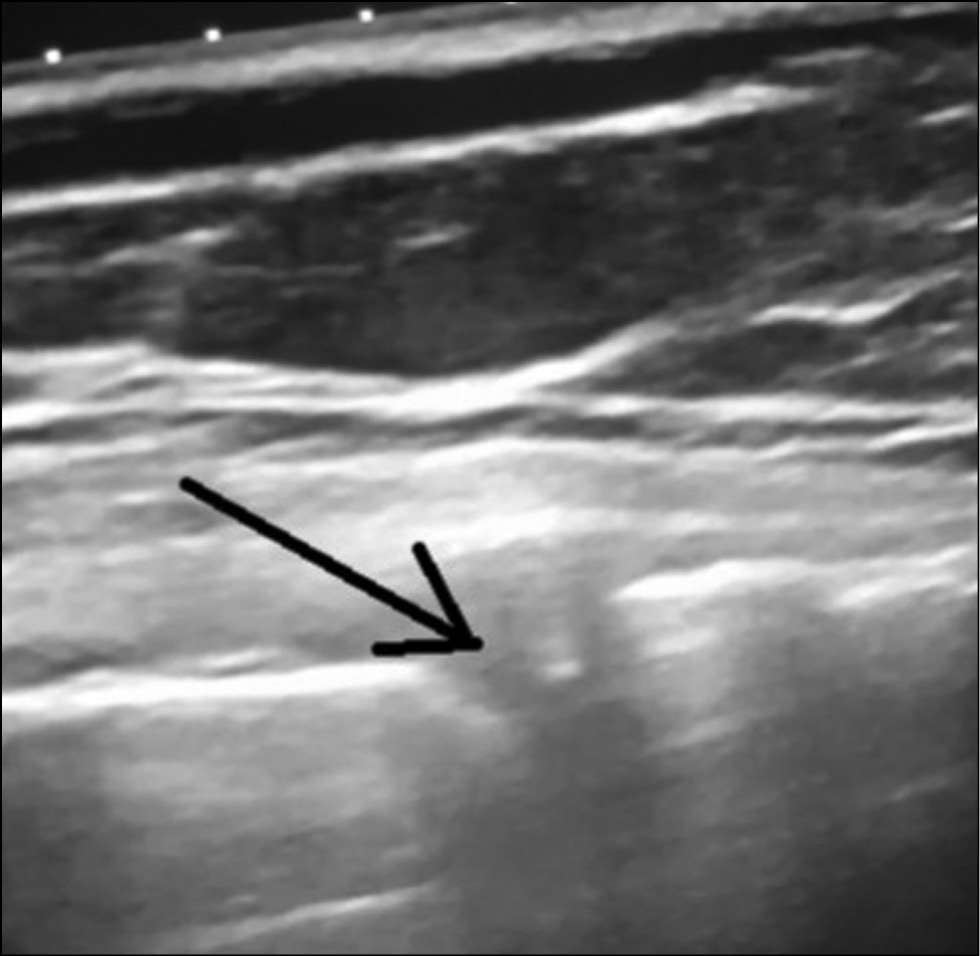

A suspension of platelets (approximately 0.5 mL) is injected into the region of the posterior horn under US control. A small amount (approximately 0.2 mL) is also injected into the border precapsular zone of the joint (Fig. 4). After the procedure, the patients remained in the outpatient department for 2 h.

Fig. 4. The introduction of the needle into the meniscus under ultrasound control (the arrow indicates the needle).